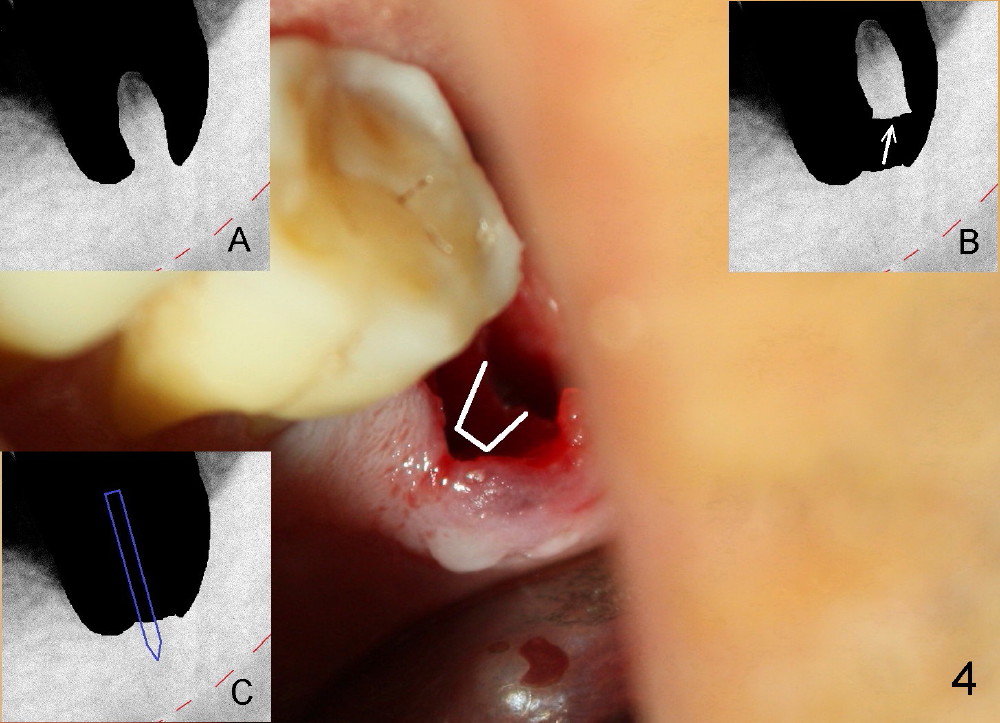

A 51-year-old man has generalized chronic periodontitis. The mesial root of #18 has vertical fracture (Fig.1*) with infection. The patient agrees extraction (Fig.2) and immediate implant. The septum is thin. The pilot drill drops into either the mesial (Fig.3) or distal sockets. Furthermore it is difficult to control pain probably due to severe infection (Fig.2 >: mesiobuccal erythema and edema). Repeated local infiltration does not alleviate pain associated with drilling. Block anesthesia has to be administered (one carpule of 2% Lidocaine with 1:100,000 Epinephrine). Damage to the inferior alveolar nerve (Fig.1 red dashed line) increases. On the other hand, osteotomy through the socket of the tooth with periodontits is easier because of shallow socket. Retraction of the buccal gingiva can reveal the bottom of the socket. We will increase the depth slowly until a tap obtains initial stability. The worst scenario is that active hemorrhage from the socket bottom is encountered initially. The nerve injury can be reduced minimally.

How about flatten the septum (Fig.4 white lines; from inset A (post extraction) to B)? When the septum is level with the mesial and distal sockets, a drill easily penetrates the middle of the socket (Fig.3 inset C). With strict control of depth, the osteotomy increases until a 6x14 mm tap gets initial binding to the socket (Fig.5: depth 11 mm). After increase in the depth by 1-2 mm, PA is taken with a 7x14 mm tap (Fig.6). There is a gap that the tap or the corresponding implant can engage further (between arrowheads). After increase in the diameter in the bottom of the osteotomy, a 7x11 mm implant is placed with insertion torque between 45 and 50 Ncm; the threads of the implant have tight contact with the bone (Fig.7). With the large diameter implant, the socket opening is closed without too much tension (Fig.8). The wound is protected with perio dressing. Postop there is no paresthesia. Pain is controlled by Hydrocodon/Acetaminophen. A long acting local anesthetic (Marcaine) should have been used immediately postop. Next morning, the patient is pain free. A short implant should be used in a critical area such as the lower 2nd molar where the inferior alveolar nerve is nearby. However, the implant is found unstable 1 month postop.